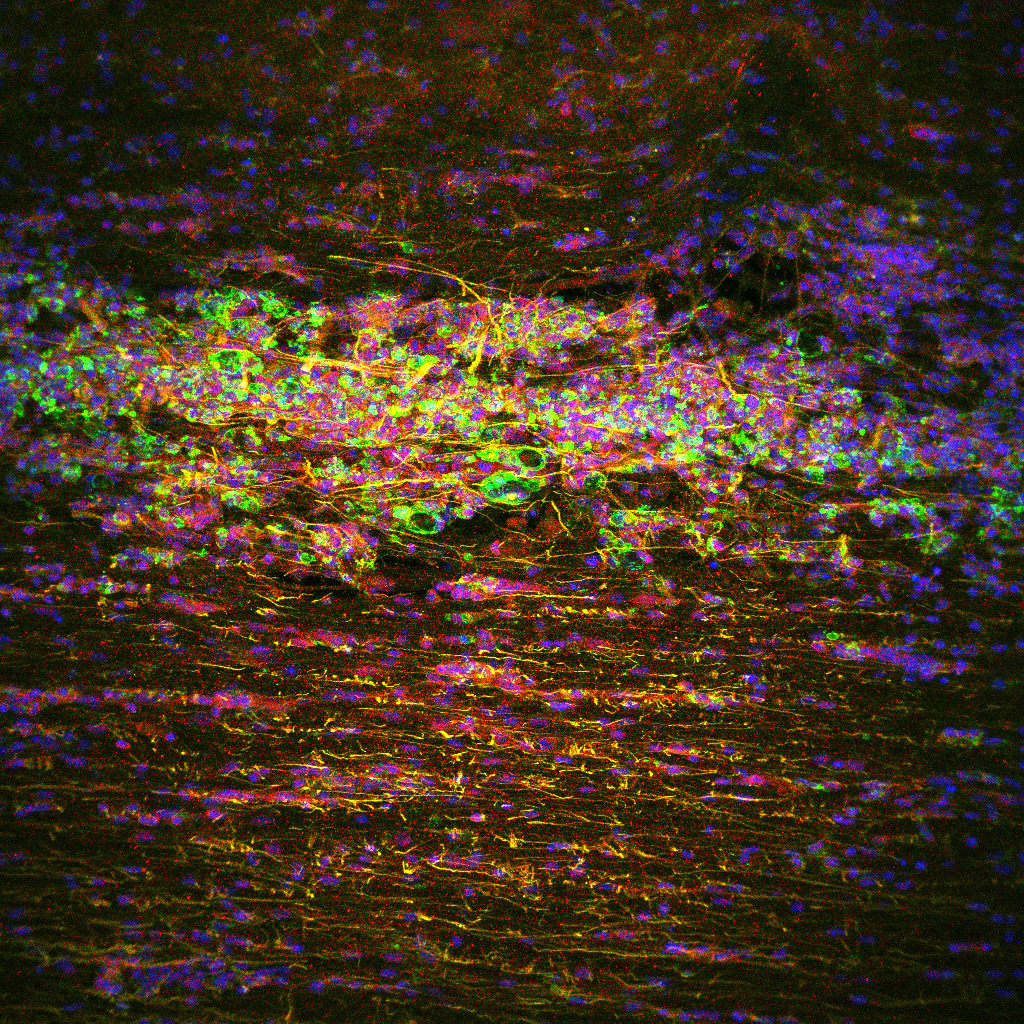

Striking Laboratory Data Images

Laboratory Data Gallery

Universe of the brain